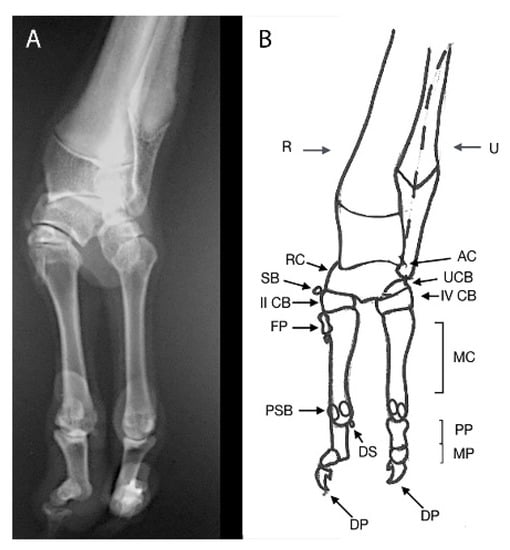

2.4. Case 2